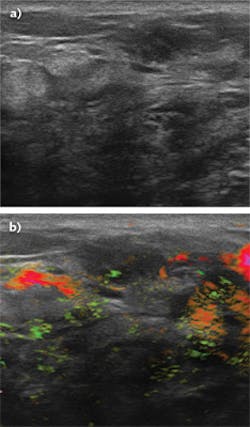

The tool, called the Imagio optoacoustic/ultrasound (OA/US) breast-imaging system, arose from the company’s desire to improve the quality of care for breast-cancer diagnosis by developing a noninvasive imaging method that would reveal growth morphology and physiology, while also providing a map of malignancy probability. Malignant growths exhibit anomalous blood circulation—they are highly vascularized to support their fast growth, and this growth also means that their blood content is typically more deoxygenated than surrounding normal tissue. To that end, the company created a laser-based system that is coregistered to a standard grayscale ultrasound, called Imagio, which can map both vascular density and local blood oxygenation.

The system combines optoacoustic technology with B-mode ultrasound (see figure). A handheld, fiber-coupled unit similar to a conventional ultrasound probe is scanned over the breast. In addition to ultrasound interrogation, the unit illuminates the breast with nanosecond pulses of near-infrared (near-IR) light at two separate wavelengths. These are generated from a pair of custom-designed Q-switched lasers, one Nd:YAG and the other alexandrite. The lasers are coupled to the handpiece via a fiber bundle in the system umbilical.